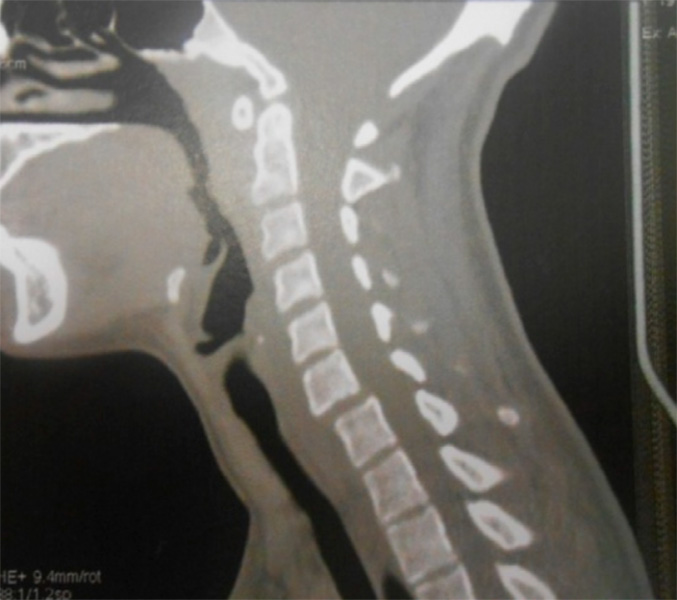

La espondilolisis cervical se define como una hendidura del istmo vertebral o espacio existente entre las faceta superior e inferior de los pilares articulares. Mientras que a nivel lumbar se ha descrito en el 5% o 6%de la población mundial a nivel cervical se considera una anomalía rara, con menos de 100 casos publicados hasta la fecha.